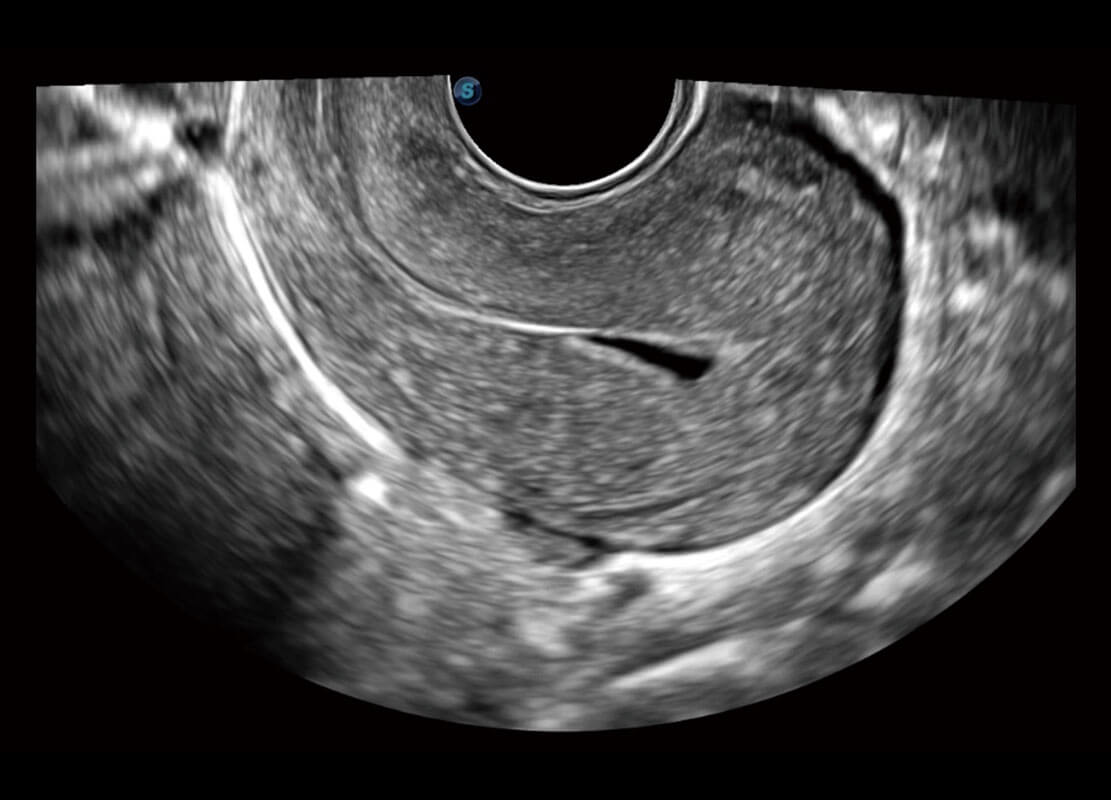

P60优异的图像质量搭载专科探头,在妇科基础疾病的诊断、卵泡生长的监测、输卵管通畅情况的判别等方面为您提供生殖应用方案。

腔内妇科-宫腔分离

腔内妇科-卵巢

腔内三维-宫内节育器

腔内三维-光影成像